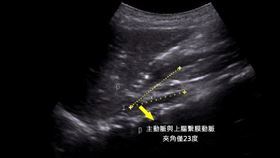

72歲的朱女士患有高血壓、糖尿病等慢性病,接受腹膜及...

2024/07/23 10:42